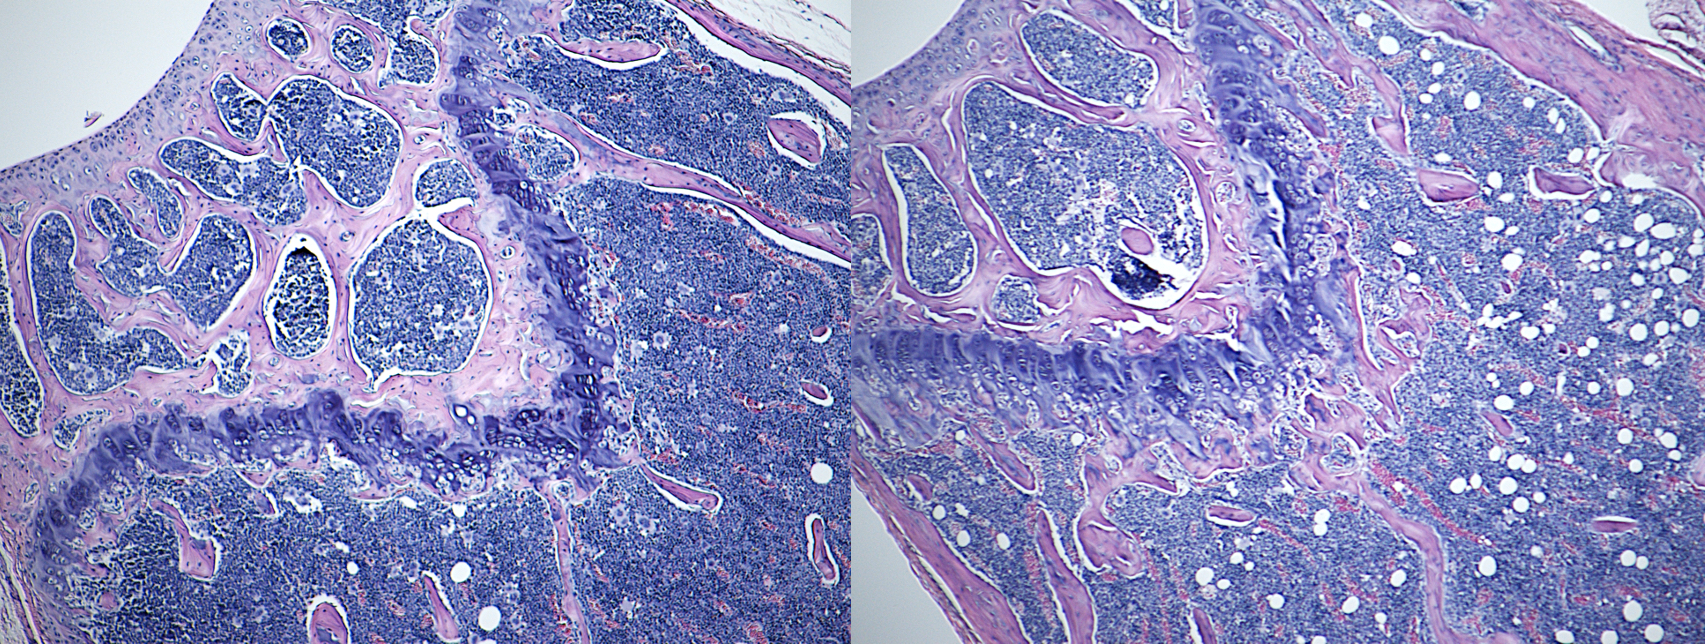

Our lab is interested in identifying genes that participate in the regulation of bone mechanical integrity and bone mass but do so via interactions with environmental modulators. We are specifically interested in determining how the in-bone actions of pharmacological factors such as Teriparatide, a PTH analog (pictured), are modified by genetic factors. In addition, we are also interested in the impact of dietary fat on osteoblast and osteocyte function in the face of allelic differences.